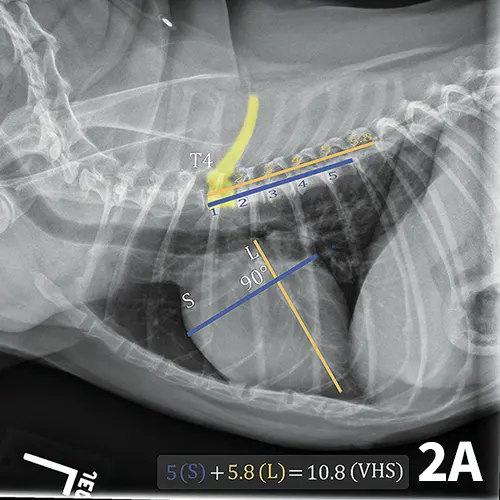

The ACVIM consensus statement on degenerative MVD recommends baseline thoracic radiography for dogs with a new murmur, then annually thereafter.6 For practitioners adhering to these guidelines, annual calculation of VHS and rate of change from previous imaging should become standard practice and may help identify those patients at higher risk of developing CHF in the coming year. Figure 2 illustrates annual radiographs taken in a patient with progressive cardiomegaly.

FIGURE 2A

Progressive cardiomegaly noted on annual evaluations in a dog with MVD.